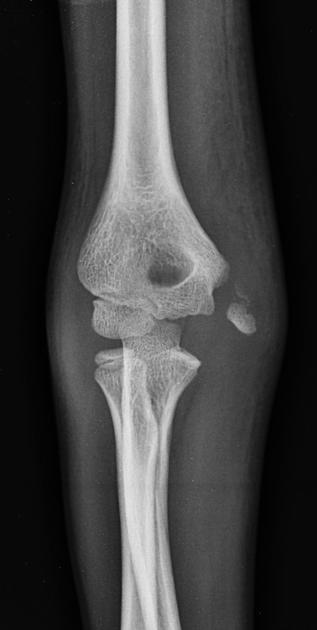

Для точного диагноза необходимо провести рентгенографию соединения плечевой, локтевой и лучевой костей в прямой и боковой проекциях.

В травматологическом отделении после рентгенографического исследования врач установит диагноз и определит необходимый объем лечения.